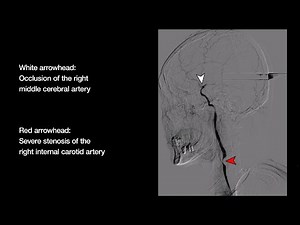

Diagnostic Cerebral Angiography